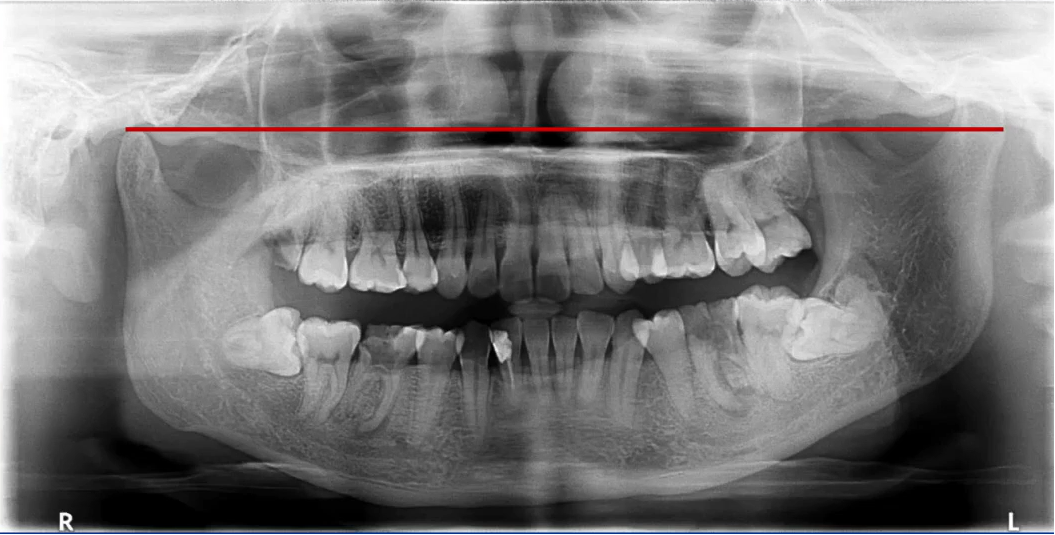

一、理想曲断影像

中线左右对称,牙齿排列呈微笑弧形,片子左右两边相对对称,能清晰显示颞下颌关节、上下牙列的牙根,图像的对比度和分辨率较好。

下图的患者牙弓整体排列呈一字型,一般认为机器伸的过高,头仰起来了,导致硬腭下降和牙根发生了重叠。

二次拍摄时使机器降低,不要让患者的头仰起来,患者的面平面与地面形成垂直型夹角,大面积重叠消失。